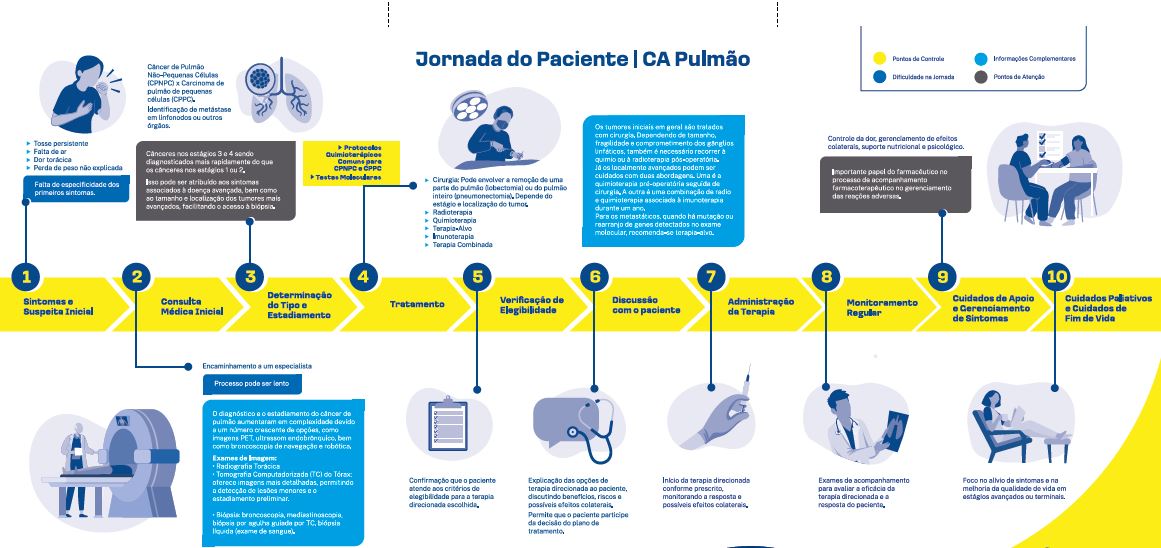

O Laboratório Eurofarma acaba de lançar o Timb: sua versão para o medicamento Gefitinibe, utilizado no tratamento de pacientes diagnosticados com câncer de pulmão de não-pequenas células (CPNPC), oferecendo um caminho promissor no combate a essa forma agressiva de câncer. Descubra neste artigo tudo sobre o Timb, desde suas indicações até os benefícios associados ao tratamento. Para profissionais da saúde, adicionamos informações e referências que podem auxiliar na escolha da medicação.

Indicações e Utilização do Timb (Gefitinibe)

Gefitinibe é um medicamento inovador indicado para o tratamento de pacientes com CPNPC localmente avançado ou metastático, que apresentam mutações de ativação do receptor de fator de crescimento epidérmico tirosina quinase (EGFR). Esta abordagem direcionada visa especificamente os casos em que a presença dessas mutações torna o tumor mais suscetível ao tratamento com Gefitinibe.

Câncer de Pulmão de Não-Pequenas Células (CPNPC): Uma Perspectiva Detalhada

O câncer de pulmão de não-pequenas células (CPNPC) é uma forma predominante de câncer pulmonar, compreendendo a maioria dos diagnósticos nessa categoria. Ao contrário do câncer de pulmão de pequenas células, o CPNPC se caracteriza por um crescimento mais lento e tende a se disseminar mais gradualmente. Essa forma de câncer é frequentemente diagnosticada em estágios avançados, quando as opções de tratamento podem ser mais desafiadoras.

As mutações no receptor de fator de crescimento epidérmico tirosina quinase (EGFR) são uma característica distintiva em alguns casos de CPNPC. Essas mutações desempenham um papel crucial no impulso do crescimento celular descontrolado, uma característica fundamental do câncer. É nesse cenário que o Gefitinibe emerge como uma terapia inovadora, mirando diretamente essas mutações para conter o avanço do CPNPC.

Benefícios do Tratamento com Timb (Gefitinibe) no CPNPC

Ao focar nas mutações de EGFR, o Timb (Gefitinibe) interrompe a cascata de eventos que impulsionam o crescimento desordenado das células cancerígenas no pulmão. Isso não apenas oferece uma abordagem mais eficaz, mas também reduz os efeitos colaterais associados a tratamentos mais amplos e generalizados.

Além disso, o Timb/Gefitinibe representa uma nova era na terapia direcionada para o CPNPC, proporcionando uma melhor qualidade de vida para os pacientes e prolongando a sobrevida em comparação com opções de tratamento convencionais.

Baixe em alta resolução: AF_FLUXO PACIENTE GEFITINIBE_OUT23_Medicom

Qual o preço do Timb (Gefitinibe)?

Você encontra o Timb (Gefitinibe) 250mg, caixa com 30 comprimidos revestidos na Farmácia Medicom com o preço de R$ 2.845.00. (valor consultado em dezembro de 2023).

1. Mecanismo de ação e indicação

O Timb/gefitinibe é um inibidor de tirosina quinase (TKI) indicado para o tratamento de pacientes com câncer de pulmão não-pequenas células localmente avançado ou metastático, que apresentam mutações de ativação no receptor do fator de crescimento epidérmico (EGFR).